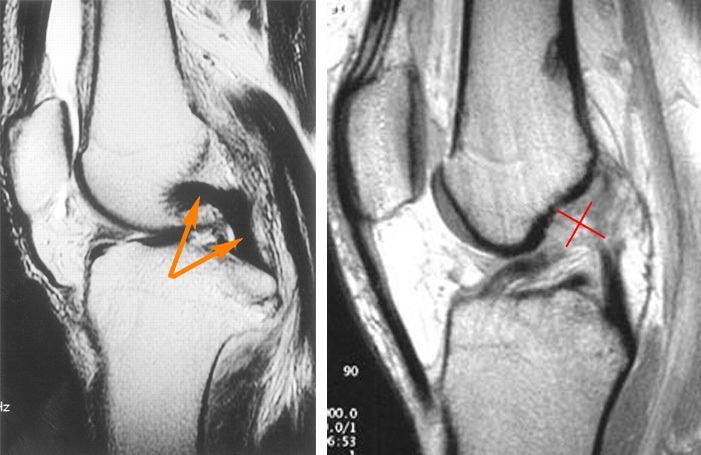

Для окончательной диагностики назначают дополнительные исследования, такие как МРТ, КТ, УЗИ, рентген и артроскопия.

Наиболее информативным методом является МРТ, так как она позволяет получить полное представление о состоянии всех компонентов сустава: менисков, хрящей, жировой и костной тканей, сосудов, связок и сухожилий. Если требуется оценить только состояние костной ткани, назначают рентгенографию.